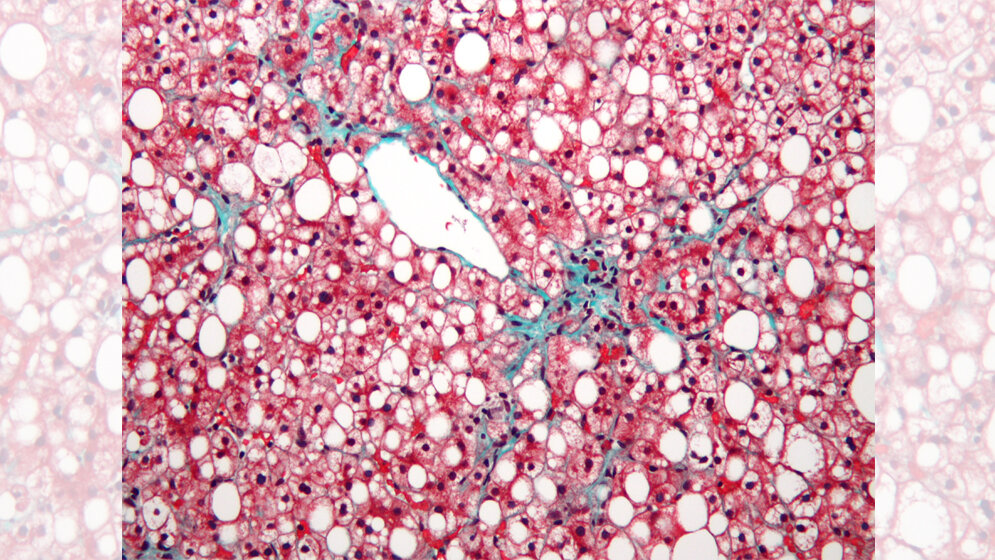

Mehr als die Hälfte der Erwachsenen und ein Drittel der Kinder in Europa gelten als übergewichtig oder adipös, wobei der höchste Anteil in den unteren sozioökonomischen Gruppen zu finden ist, in denen die nicht-alkoholische Fettlebererkrankung vorherrscht. Bei der nicht-alkoholischen Fettleber bzw. NAFLD handelt es sich um die Ansammlung überschüssigen Fetts in der Leber. Das Krankheitsbild gilt heutzutage aufgrund des rasanten Anstiegs von Adipositas und Typ-2-Diabetes als die häufigste Ursache für Lebererkrankungen in westlichen Ländern. Sie stellt eine wesentliche gesundheitliche Belastung in Europa dar und kann zu Leberzirrhose und Leberkrebs führen sowie zu einem starken Anstieg bei Herz-Kreislauf- und anderen Krebserkrankungen.